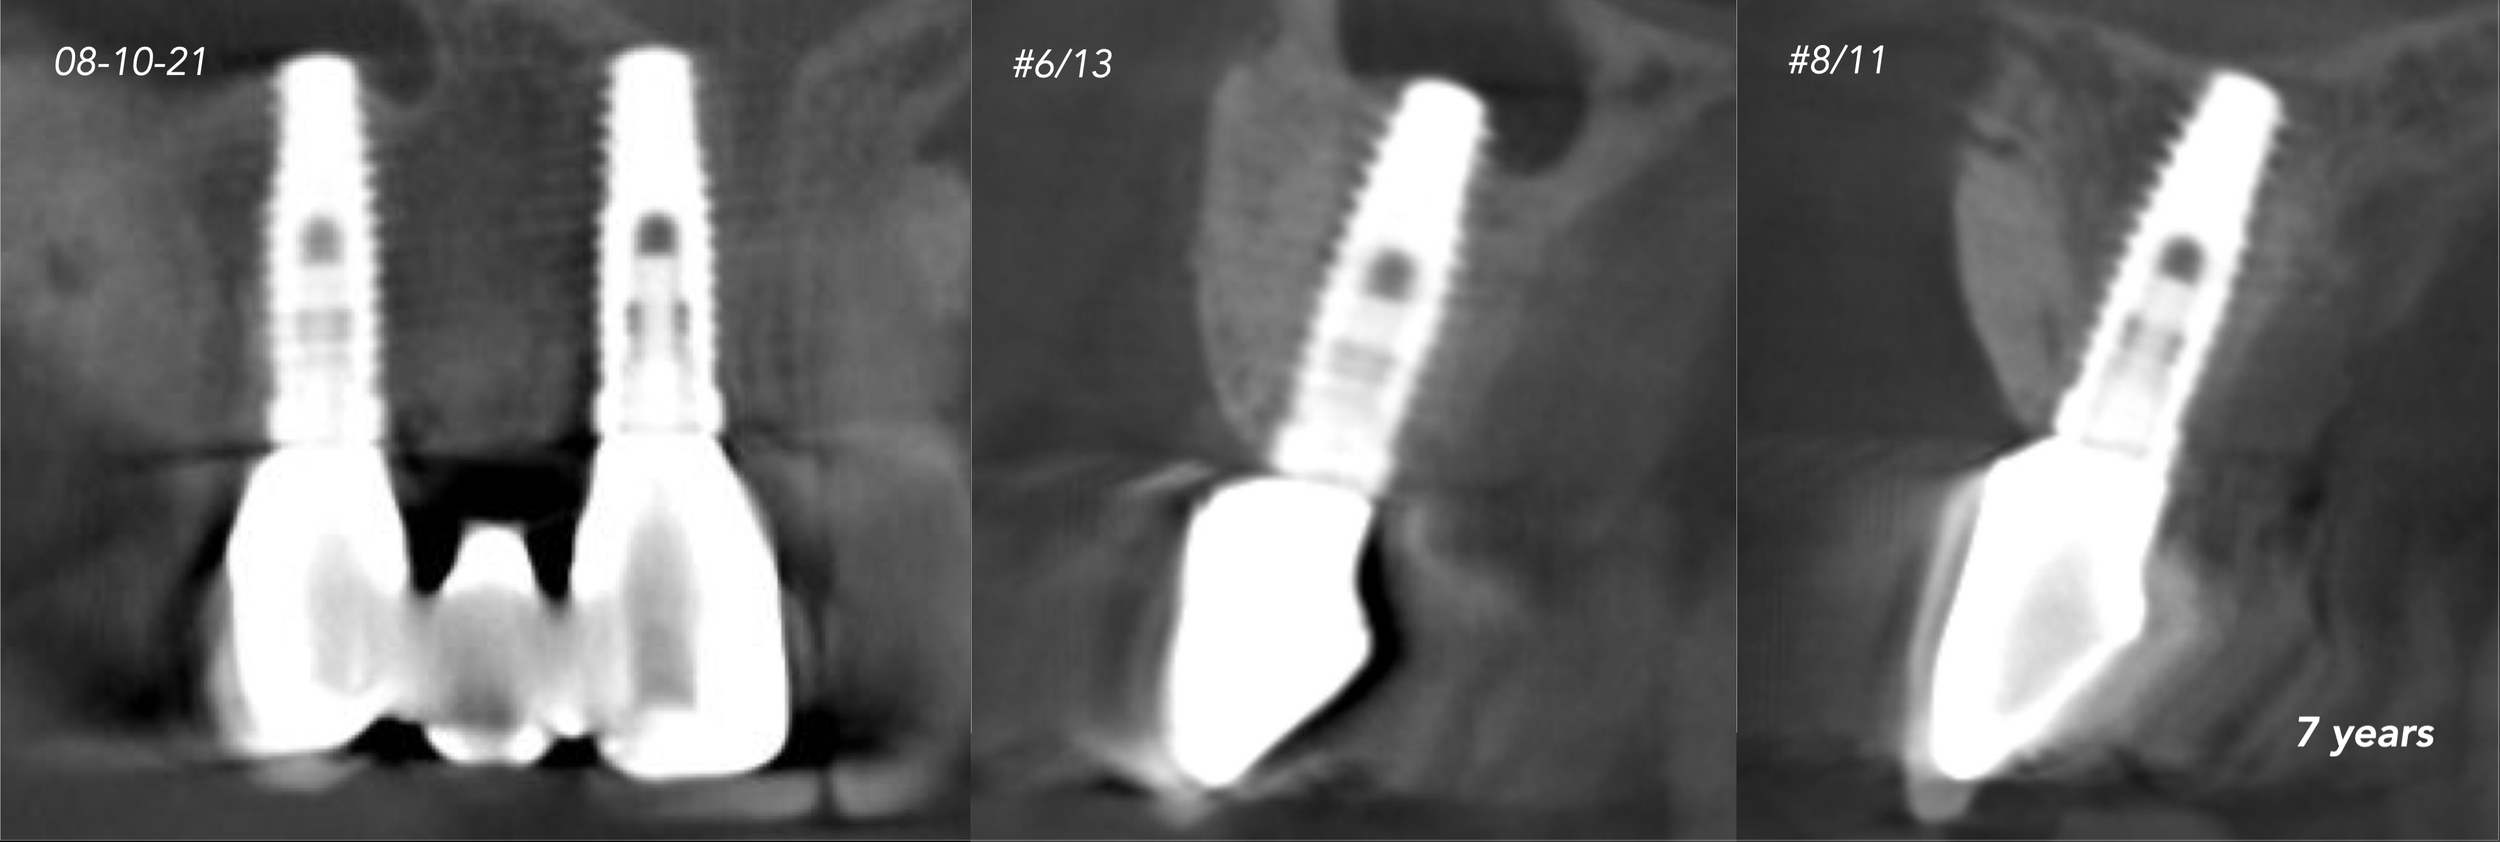

CASE 1. COMPLEX IATROGENIC DEFECT